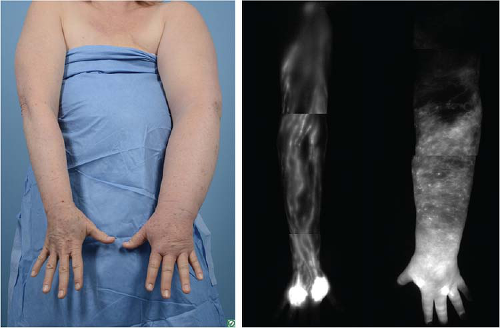

More recently and currently off-label but commonly used among lymphatic surgeons, is indocyanine green (ICG) lymphography (8). This involves subdermal injection of ICG which is taken up by the lymphatic vessels and using a near-infrared camera, a high-resolution image of the lymphatic system itself is seen. Abnormalities of the lymphatic vessels are directly and clearly visualized. A complete absence of lymphatic vessels of the lymphatic system is seen in Figure 25-1. Imaging studies are best used to confirm a diagnosis in cases which are unclear or in preparation for lymphatic surgery. In summary, patient-reported symptoms often present much earlier than visible swelling and should prompt referral for lymphedema therapy. Screening with symptoms and/or BIS at the patient’s postop oncologic follow-up appointment every 6 months is a reasonable starting point for lymphedema surveillance in high-risk patients.

![]() FIGURE 25-1 Clinical photo compared to ICG lymphangiography demonstrating advanced lymphedema with no lymphatic vessels visualized. Not an ideal candidate for lymphovenous bypass. |